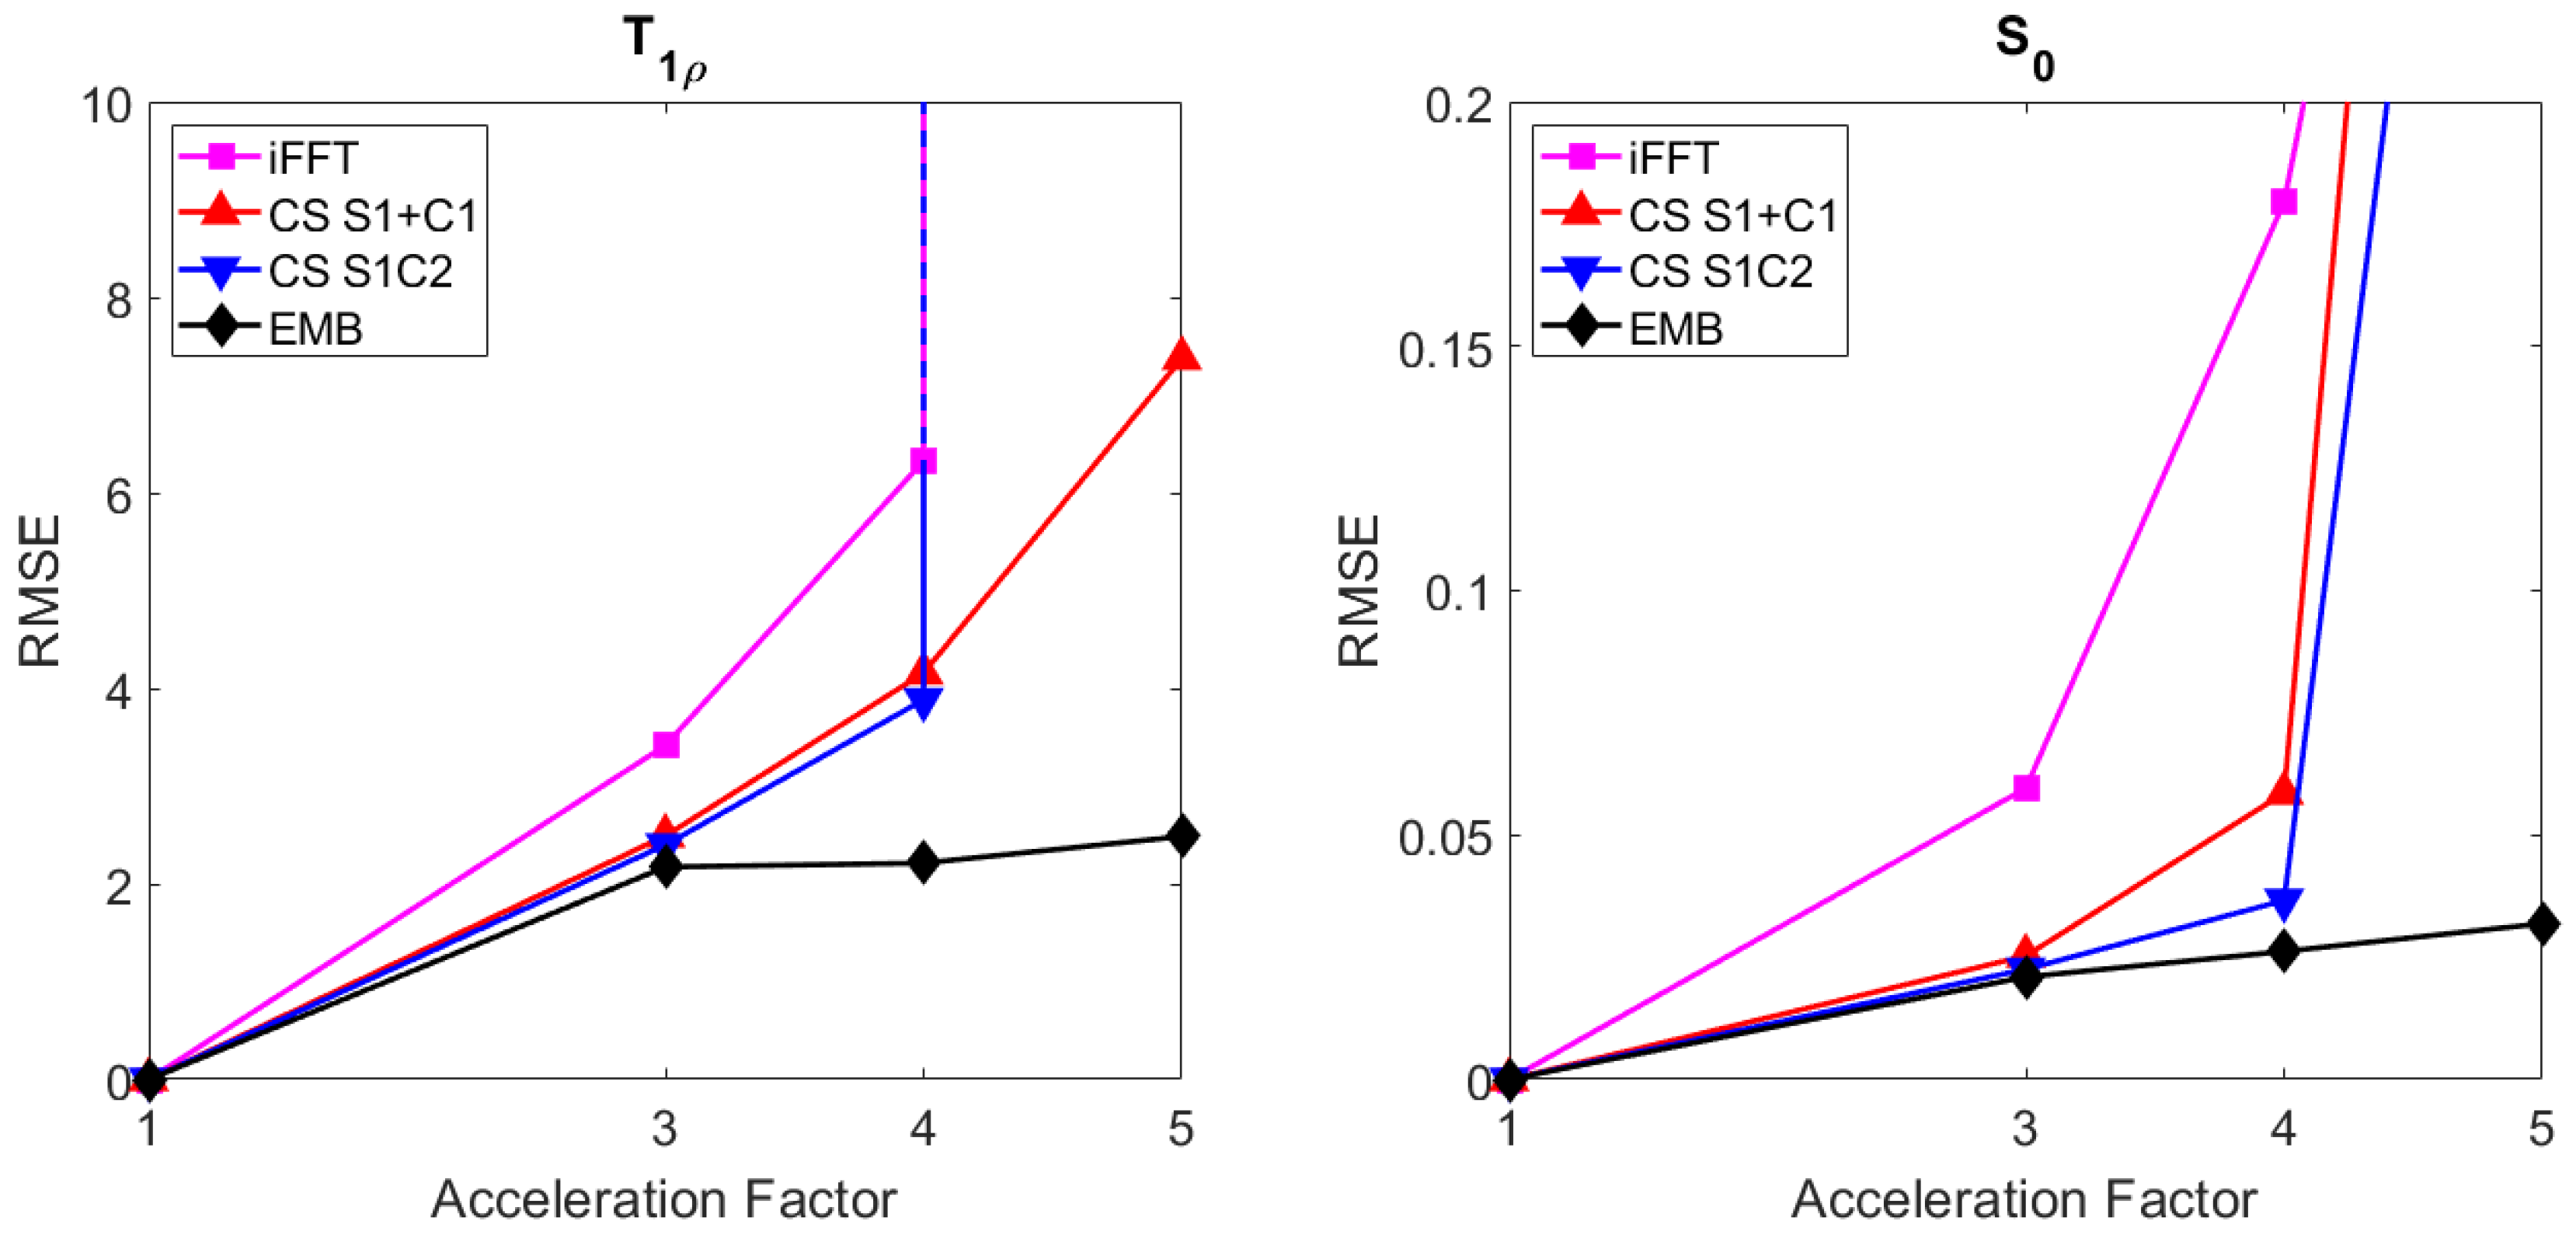

4.1. Simulated Golden Angle Radial Data